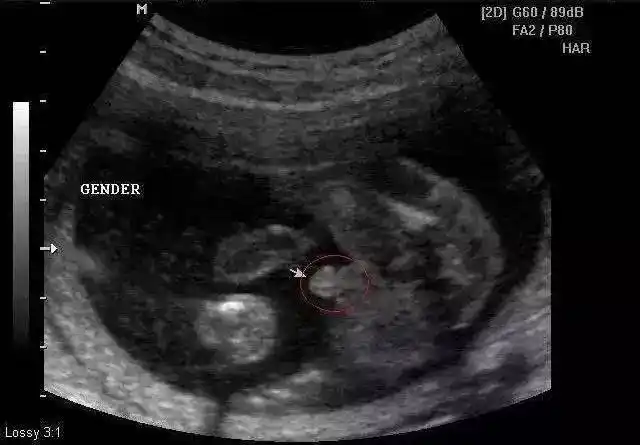

怀孕十二周可以从b超中的小肿块分辨男女,这真的可以看出来吗?

12周胎儿男女生殖图区别图片,nt检查看男女准不准?-医孕帮